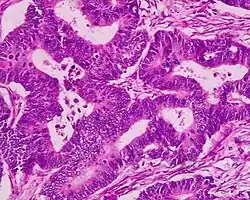

Gruczolakoraki (łac. adenocarcinomata)

Gruczolakoraki powstają najczęściej w przewodzie pokarmowym, gruczołach dokrewnych, trzustce, wątrobie, trzonie macicy, jajnikach, płucach, gruczole krokowym, śliniankach, sutku, nerkach.

Gruczolakoraki można podzielić na podstawie obrazu histologicznego, uwzględniając m.in.:

a) Stopień dojrzałości (gruczolakoraki I°, II°, III°), a zwłaszcza stopień ukształtowania struktur gruczołowych (histioformatywność):

- gruczolakorak (łac. adenocarcinoma) – struktury gruczołowe bardzo dobrze widoczne,